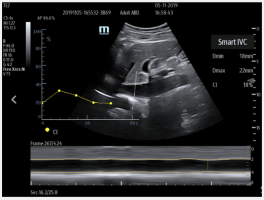

Smart Inferior Vena Cava (Smart IVC) – Automated measurement of Inferior Vena Cava (IVC) helps assess volume status and guides fluid management. A trending graph documents the change in collapsibility (CI) and distensibility (DI) to document fluid response over time and guide therapy.

Smart Inferior Vena Cava (Smart IVC) – Automated measurement of Inferior Vena Cava (IVC) helps assess volume status and guides fluid management. A trending graph documents the change in collapsibility (CI) and distensibility (DI) to document fluid response over time and guide therapy.